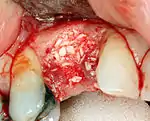

Hard tissue (bone) reconstruction

Bone grafting is necessary when there is a lack of bone. Also, it helps to stabilize the implant by increasing survival of the implant and decreasing marginal bone level loss.[41] While there are always new implant types, such as short implants, and techniques to allow compromise, a general treatment goal is to have a minimum of 10 mm (0.39 in) in bone height, and 6 mm (0.24 in) in width. Alternatively, bone defects are graded from A to D (A=10+ mm of bone, B=7–9 mm, C=4–6 mm and D=0–3 mm) where an implant's likelihood of osseointegrating is related to the grade of bone.[42]: 250

To achieve an adequate width and height of bone, various bone grafting techniques have been developed. The most frequently used is called guided bone graft augmentation where a defect is filled with either natural (harvested or autograft) bone or allograft (donor bone or synthetic bone substitute), covered with a semi-permeable membrane and allowed to heal. During the healing phase, natural bone replaces the graft forming a new bony base for the implant.[38]: 223